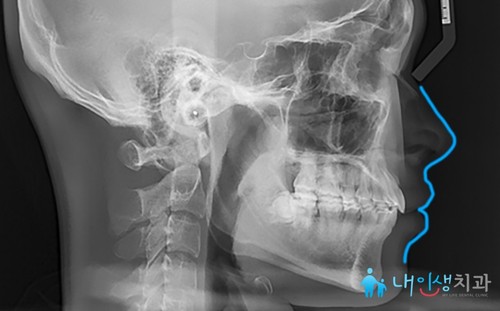

<진료 종료>

서초치아교정을 시작한 뒤

1년 5개월이 지나고

진료를 최종 마무리한 모습입니다.

치아 중심선이 맞춰지고

배열도 가지런해진 결과를

확인하실 수 있어요.

앞니 각도가 크게 틀어지면서

입술이 돌출되는 증상을 보이셨는데,

전치부가 안정적으로 들어간 모습을

보실 수 있죠.

X-ray 전후 사진도 함께 살펴볼게요.

뻐드러졌던 앞니 각도가

자연스럽게 맞춰진 것을 확인할 수 있습니다.

틀어진 치아로 인해 입술이 많이 돌출되고

입을 다문 모습도 부자연스러웠는데

교정 치료를 통해 말끔하게

해결된 모습이에요.